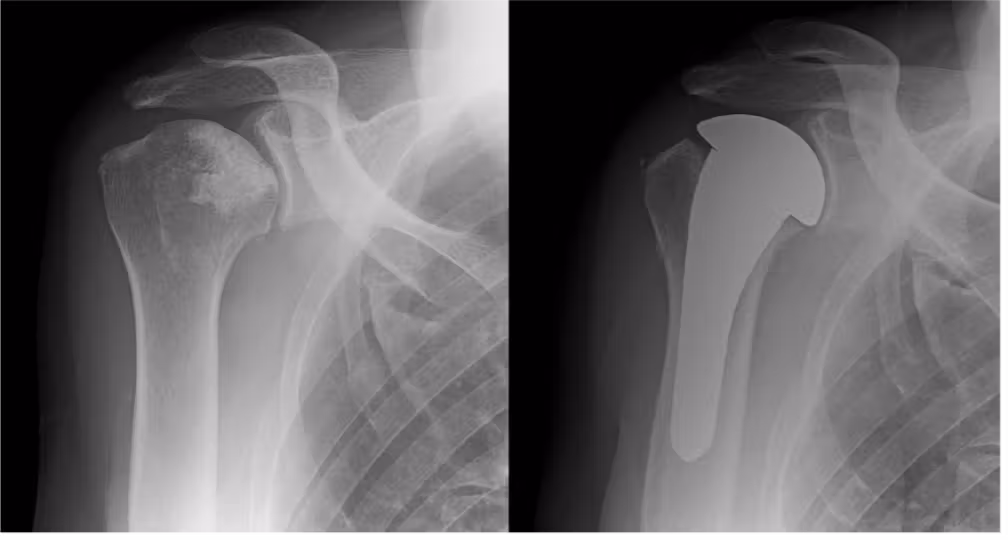

上腕骨頭壊死症に対する人工骨頭挿入術